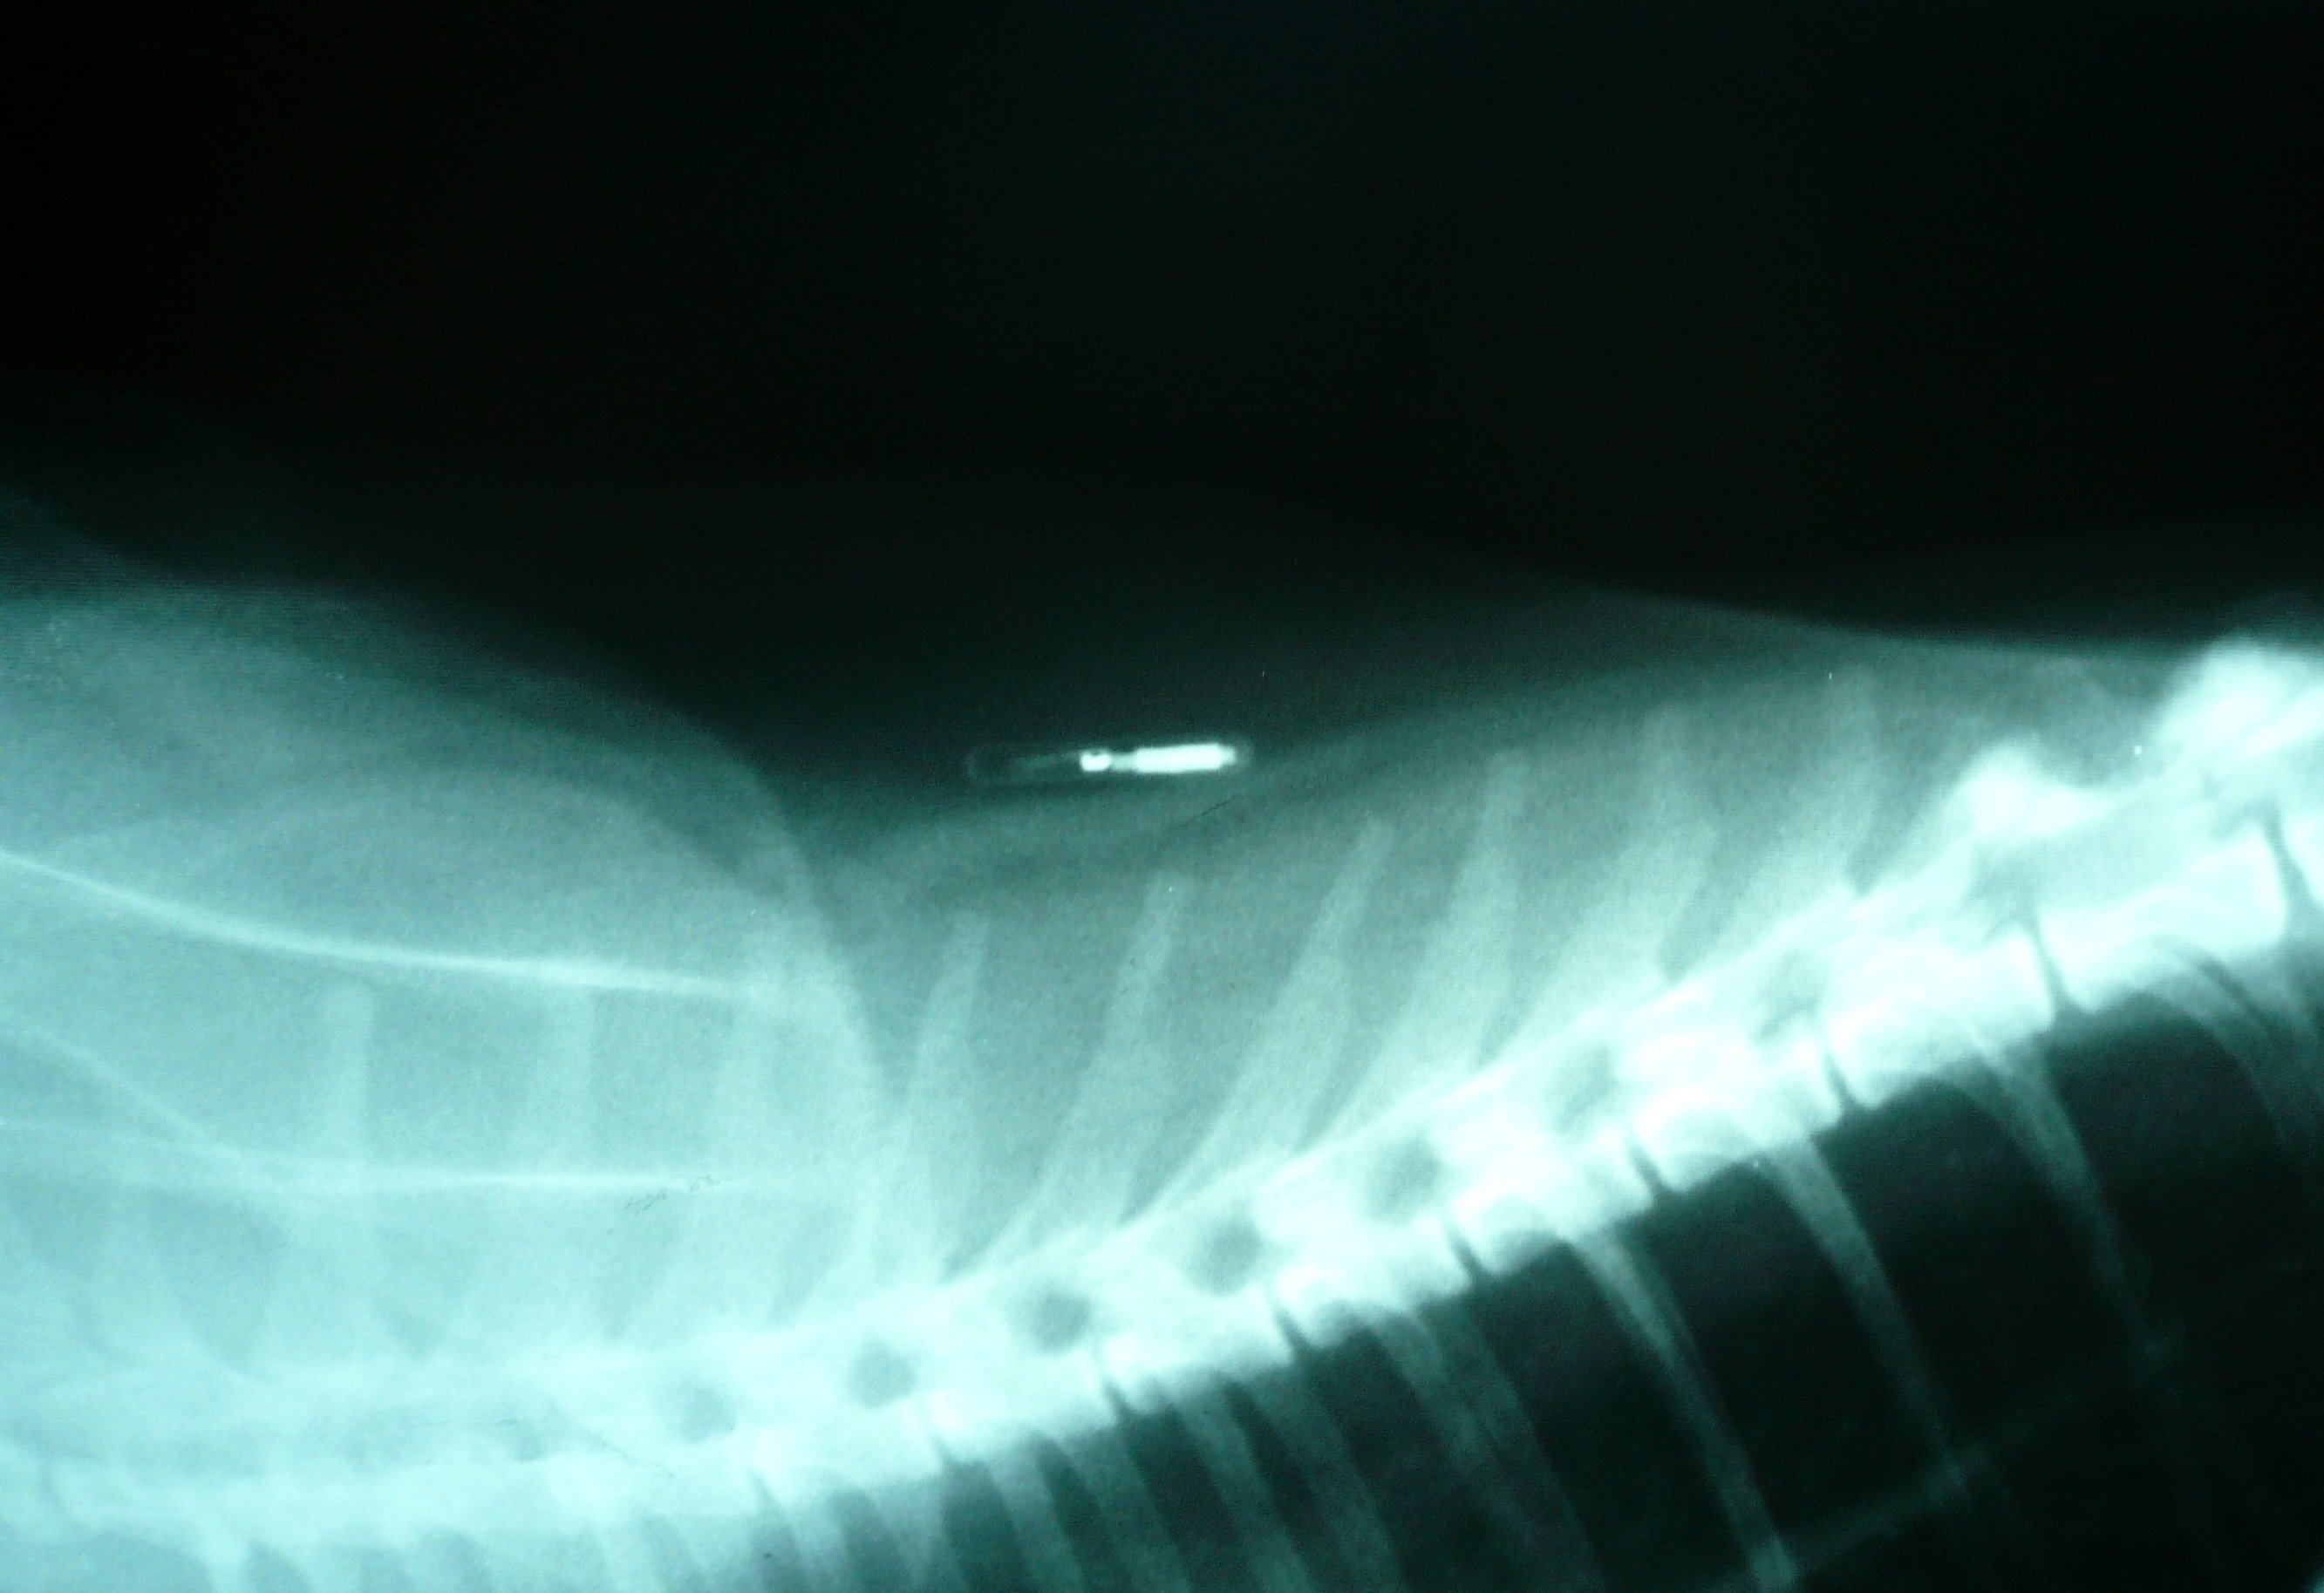

Dogs and cats are from different species of animals, appealing to different types of people. Even though each species has its own distinct looks and characteristics. Registering your pets' microchip is as . When the microchip is scanned by a vet or shelter, it transmits the id number. For dogs, the standard site for microchip placement is in the subcutaneous tissue along the dorsal midline (the spine) between the dog's shoulder blades.

The microchip implant process is not a surgery and requires . A pet microchip is a tiny computer chip that's about the size of a. When the microchip is scanned by a vet or shelter, it transmits the id number. Registering your pets' microchip is as . There's no battery, no power required, and no moving parts. See how easy and quick it is. Description and location so that they may notify the owner or contact. Man’s best friend has a funny way of communicating sometimes, but almost everything your dog does has meaning. In cats and dogs, the microchip is typically implanted between the shoulder blades. The microchip is implanted between the animal's shoulder blades under the skin with a needle and special syringe. The process is similar to . For dogs, the standard site for microchip placement is in the subcutaneous tissue along the dorsal midline (the spine) between the dog's shoulder blades. Dogs and cats are from different species of animals, appealing to different types of people.